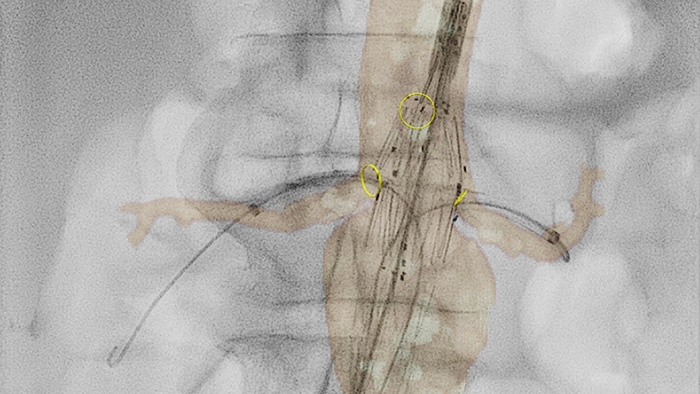

VesselNavigator ermöglicht die Wiederverwendung von dreidimensionalen Gefäßanatomiedaten aus bestehenden CTA- und MRA-Datensätzen als 3D-Roadmap-Überlagerung auf einem Echtzeit-Röntgenbild. Dank der hervorragenden Darstellung kann VesselNavigator kontinuierlich eine intuitive 3D-Roadmap als Führungshilfe bei der Navigation durch Gefäßstrukturen bieten.

SmartCT Roadmap bietet eine Live-3D-Bildüberlagerung, die segmentiert werden kann, um Zielgefäß und -läsionen hervorzuheben und so eine schnelle Katheterisierung zu unterstützen. SmartCT Roadmap überlagert 3D-Rekonstruktionen des Gefäßbaums, der Gefäßsegmente oder der Herzschlagbeschriftungen mit Echtzeit-Durchleuchtungsbildern.